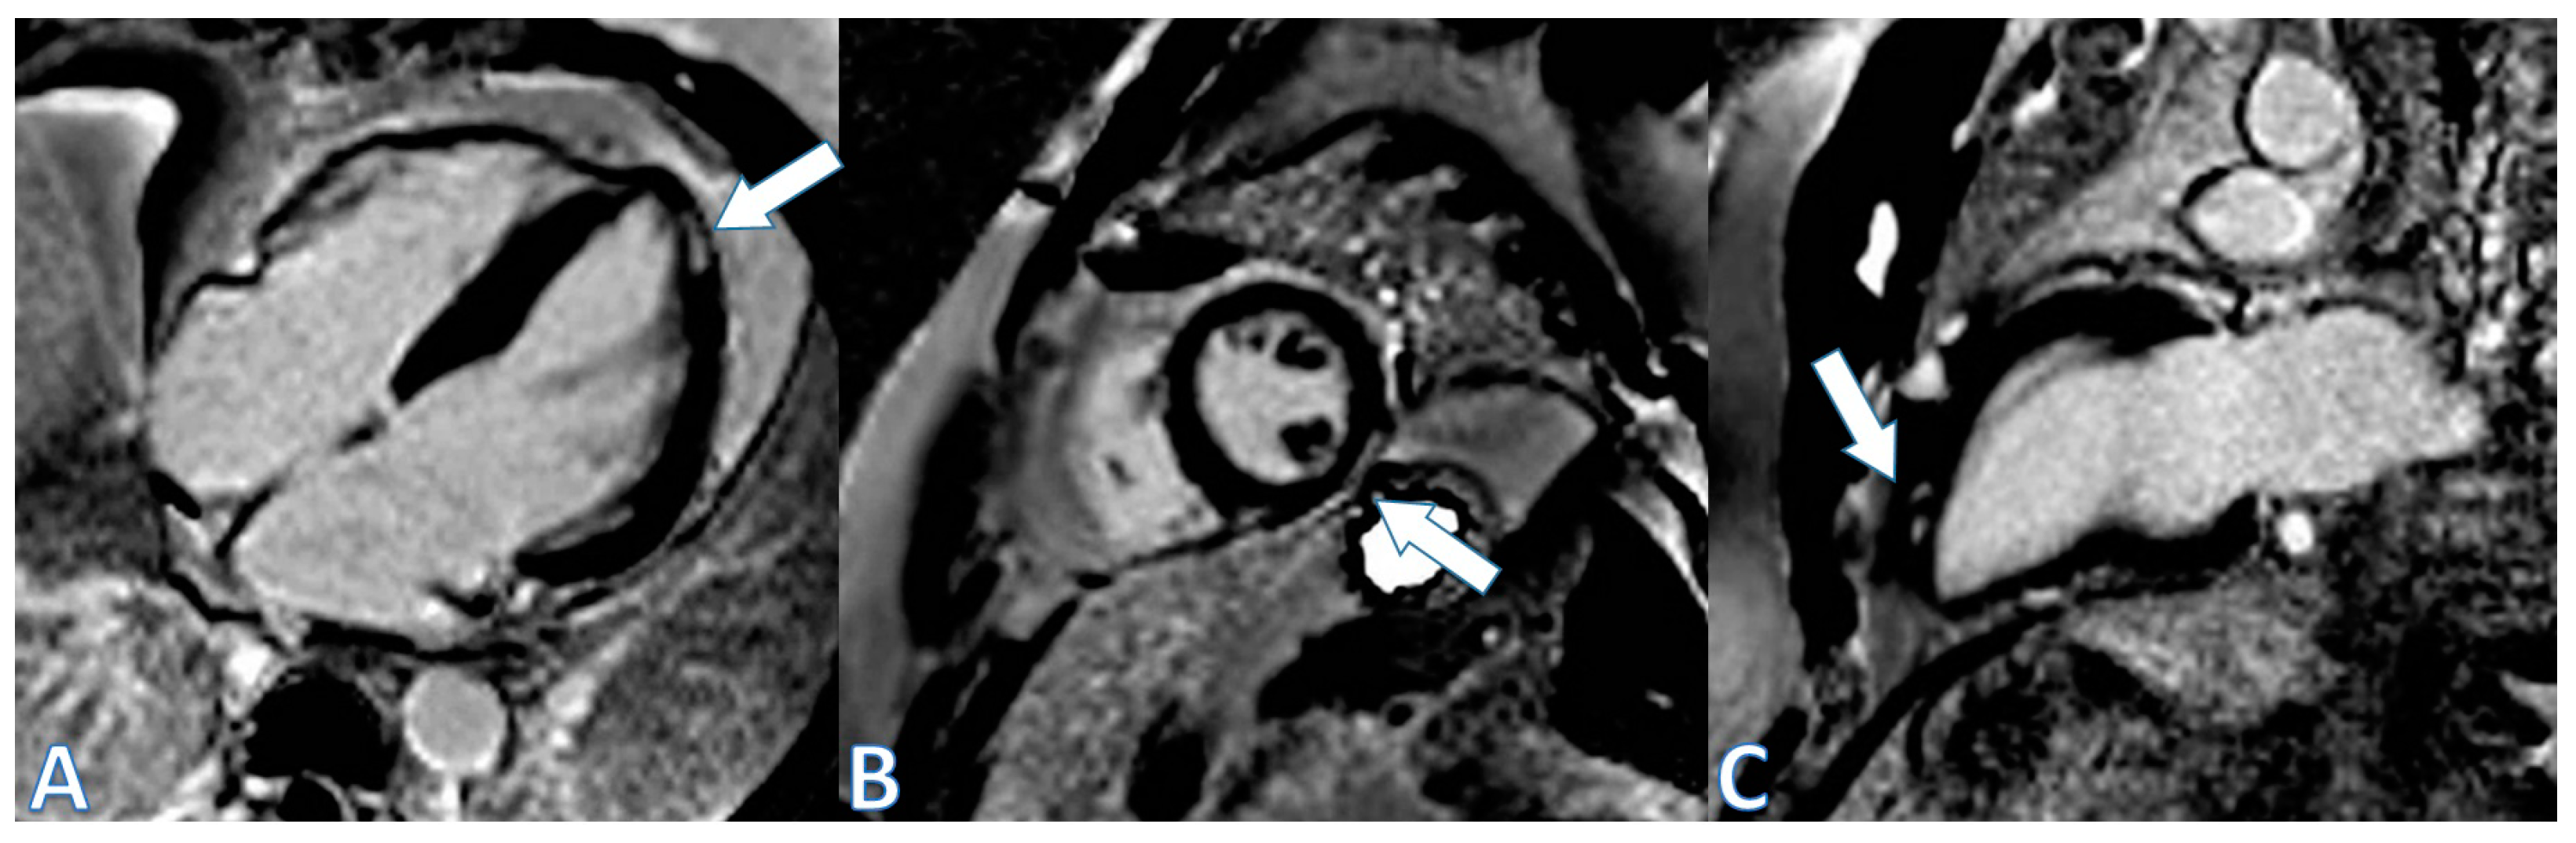

| CMR at hospitalization | LGE of both pericardial leaves and foci of late subepicardial enhancement on the basal inferolateral, lateral, and inferior walls | LGE at the level of the pericardial leaves and a basal inferolateral subepicardial focus | Edema and LGE in the lower-middle, inferolateral, and anterolateral segments | Edema and LGE at the anterolateral, basal-mid inferolateral and basal inferior segments, and intramyocardial in the mid-inferoseptal and apex segments |

| Control CMR at 6–9 months | Persistence of LGE on the inferolateral wall | - | LGE in the inferolateral and anterolateral walls | LGE intramyocardial and subepicardial at inferolateral, anterolateral, and inferoseptal walls (reduced extent) |

| Control CMR at 2 years | - | - | LGE in the inferolateral and anterolateral walls (reduced extent) | - |